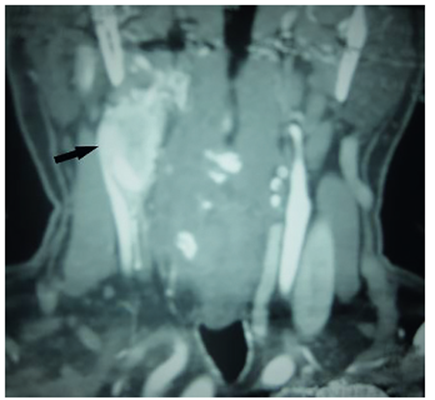

Se procedió a realizar un test de oclusión carotidea y una nueva cirugía, mediante abordaje por mandibulotomía y resección en bloque del tumor, con derivación carotidea intraoperatoria y reconstrucción con injerto de PTFE-e (figura 8), además de vaciamiento de cuello. El posoperatorio fue satisfactorio y la patología confirmó un carcinoma del glomus carotideo metastásico a 1 de 27 ganglios. Recibió radioterapia postquirúrgica IMRT 60 GY, en el seguimiento mediante un Octreoscan se encontraron metástasis hepáticas positivas (figura 9). Recibió somatostatina sistémica con excelente respuesta. Al año de seguimiento presentaba una enfermedad metastásica estable.